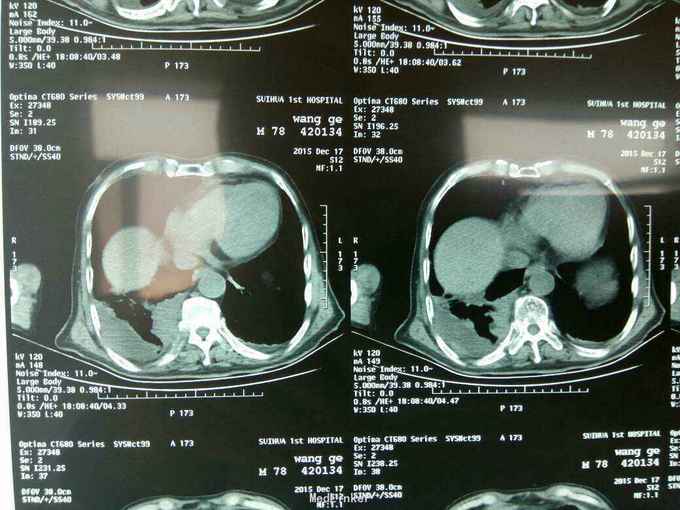

根据病史查体诊断:腰间盘突出症待确诊。应用消肿营养神经镇痛治疗。一天。查核磁共振示:腰椎多节段间盘突出伴椎管狭窄。第二腰椎骨破坏侵及椎板。部分突入椎管,脊髓受压。诊断:腰间盘突出伴椎管狭窄。第二腰椎转移癌,脊髓受压。经与家属沟通,查双肺CT:双肺下叶炎症。肺部纤维化。可见肿瘤阴影。肋骨及胸膜受累。胸椎部分骨破坏。最终诊断:双肺癌,胸椎,腰椎骨转移,脊髓受压。多节段腰椎间盘突出。病人至肿瘤科治疗。